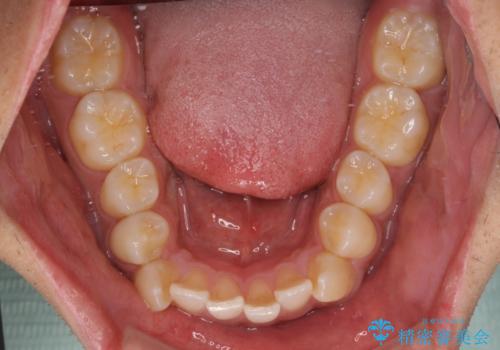

上下の前歯部に強い叢生(ガタガタの歯並び)があり、そのまま歯を並べると出っ歯になってしまう可能性がありました。

そこで、上下左右の第一小臼歯を抜歯し、歯が並ぶためのスペースを確保し叢生を解消する治療計画を立てました。

八重歯はきれいに整い、前歯もバランスよく収まり、横顔のラインも自然に改善されました。